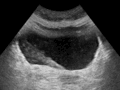

رونگاره و شمای کلیه.